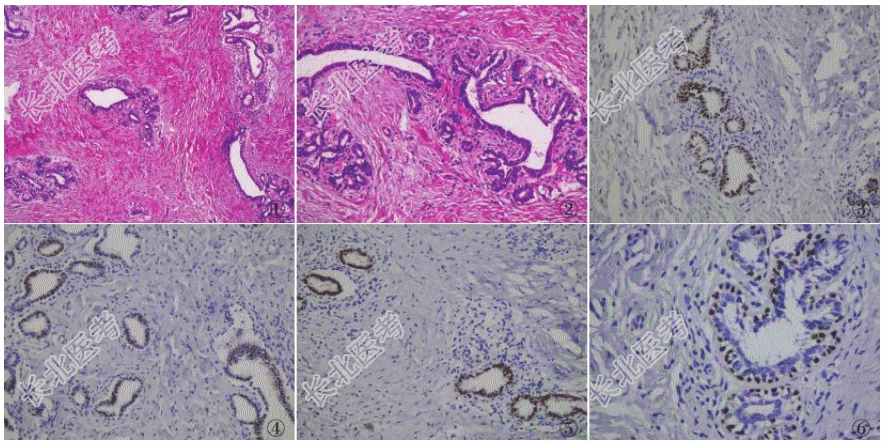

- [材料题] 患者女性,41岁,因外阴肿物3年就诊。妇科检查:右侧大阴唇外侧皮下触及大小1cm×1cm肿块,表面皮肤色泽正常,肿物略高出皮面,质偏硬,轻压痛,界限清,移动度可。遂行外阴肿物剥除术,术中见肿块位于右侧大阴唇外侧皮下,质较硬,与周围组织分界清楚,肿块表面包膜完整。眼观:灰白色肿物1枚,大小1cm×1cm×0.5cm,包膜完整,切面灰白色,质韧。镜检:低倍镜下肿瘤由上皮和间叶成分构成,上皮成分类似乳腺小叶结构,间质纤维胶原组织增生,围绕在小叶末端小导管和腺泡周围(图1),形态学类似乳腺的管周型纤维腺瘤;高倍镜下小叶内的导管和腺泡均由内层的腺上皮和外层的肌上皮构成,腺上皮细胞核圆形,可见小核仁,胞质嗜酸且丰富,可见顶泌反应,腺腔内有红染的分泌物(图2)。免疫表型:内层腺上皮表达ER(图3)、PR(图4)和GaTa3(图5),外层肌上皮表达P63(图6)。

病理诊断:外阴纤维腺瘤,来源于特化的肛门生殖器乳腺样腺体。